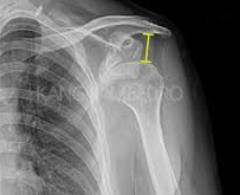

어깨탈구는 일상생활에서 누구나 경험할 수 있는 흔한 부상 중 하나입니다. 이는 어깨 관절이 정상적인 위치에서 벗어나는 상태를 말하며, 갑작스러운 충격이나 부적절한 움직임으로 인해 발생할 수 있습니다. 증상으로는 심한 통증, 움직임의 제한, 팔의 변형 등이 있으며, 경우에 따라서는 신경 손상이나 혈관 손상을 동반하기도 합니다. 치료 방법은 탈구의 정도와 환자의 상태에 따라 달라지지만, 일반적으로는 관절을 원래 위치로 복원하는 정복술과 통증 관리, 그리고 재활 운동이 포함됩니다. 이 글에서는 어깨탈구의 증상을 인식하는 방법과 효과적인 치료 접근법에 대해 자세히 알아보겠습니다. 오늘은 어깨탈구 증상 및 치료방법에 대해 알아보겠습니다.

어깨탈구는 어깨 관절이 정상적인 위치에서 벗어나는 상태를 말합니다. 이는 갑작스러운 충격이나 부상으로 인해 발생할 수 있으며, 심한 통증과 함께 어깨의 움직임이 제한됩니다. 증상으로는 어깨의 변형, 팔을 움직일 때의 고통, 그리고 팔의 힘이 약해지는 것 등이 있습니다. 치료 방법은 탈구의 정도와 환자의 상태에 따라 달라지지만, 일반적으로는 물리치료, 슬링 착용, 때로는 수술이 필요할 수도 있습니다. 이 글에서는 어깨탈구의 증상을 자세히 알아보고, 효과적인 치료 방법에 대해 탐구해보겠습니다. 어깨탈구의 이해를 통해, 이러한 부상을 예방하고, 만약 발생했을 때 적절히 대처하는 방법을 배울 수 있을 것입니다.

어깨탈구는 어깨 관절이 정상적인 위치에서 벗어나는 상태를 말합니다. 이는 다양한 원인으로 발생할 수 있으며, 통증과 함께 어깨의 움직임이 제한될 수 있습니다. 어깨탈구의 주요 증상으로는 다음과 같은 것들이 있습니다:

1. 갑작스러운 심한 통증: 탈구가 발생하면 어깨 주변의 신경이 자극되어 강한 통증을 느낄 수 있습니다.

2. 어깨의 변형: 탈구된 어깨는 비정상적인 모양을 보이거나 팔이 정상적인 위치에 있지 않게 됩니다.

3. 움직임의 제한: 탈구된 관절은 움직임이 제한되며, 때로는 팔을 전혀 움직일 수 없게 됩니다.

4. 부기 및 멍: 탈구 부위에 혈관이 손상되어 부기나 멍이 생길 수 있습니다.

5. 근육 경련: 탈구된 관절 주변의 근육이 경련을 일으킬 수 있습니다.

어깨탈구는 의학적 평가와 치료가 필요한 상태입니다. 증상이 나타나면 즉시 의료 전문가의 도움을 받아야 합니다. 자가 치료를 시도하지 말고, 전문가에 의한 적절한 진단과 치료를 받는 것이 중요합니다. 어깨탈구는 적절한 치료를 통해 회복될 수 있으며, 재발 방지를 위한 예방 조치도 필요합니다.